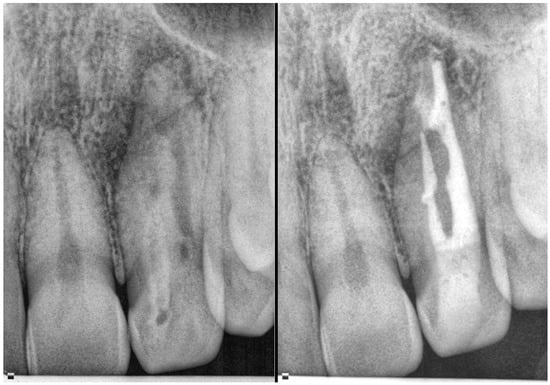

- Martins, J.N.; da Costa, R.P.; Anderson, C.; Quaresma, S.A.; Corte-Real, L.S.; Monroe, A.D. Endodontic management of dens invaginatus Type IIIb: Case series. Eur. J. Dent. 2016, 10, 561–565. [Google Scholar] [CrossRef] [PubMed]

| Type IIIa/IIIb | High risk of periapical/periodontal infection | CBCT essential to determine anatomy and extent | Selective treatment of infected invagination if pulp unaffected Often requires surgical access and debridement Orthograde or retrograde obturation with biocompatible materials Combined endodontic and periodontal approach in complex cases | Prognosis depends on anatomical complexity and extent of infection Long-term monitoring essential due to risk of reinfection |